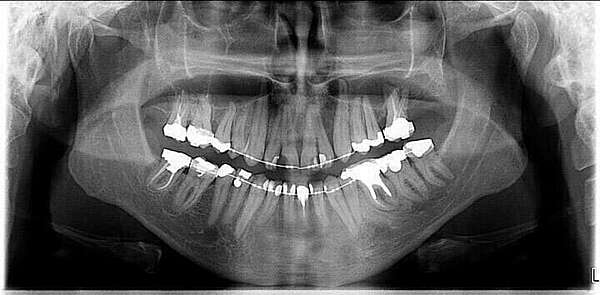

Cas 2 : Incisives trop avancées